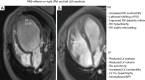

Summarizes the pulmonary artery banding (PAB) effects on the right (RV) and left ventricle (LV). (A) Depicts the magnet resonance imaging (MRI) in four-chamber view of an infant with left ventricular dilated cardiomyopathy (LV-DCM); (B) shows functional regeneration of the LV based on the PAB induced ventriculo-ventricular interaction (VVI); the MRI was performed before the PAB induced RV hypertension was unloaded by transcatheter balloon dilation. IVS, interventricular septum; LA, left atrium; MV, mitral valve; TV, tricuspid valve.